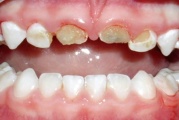

Lutipudelikaariese kahjustused

Lutipudelikaaries